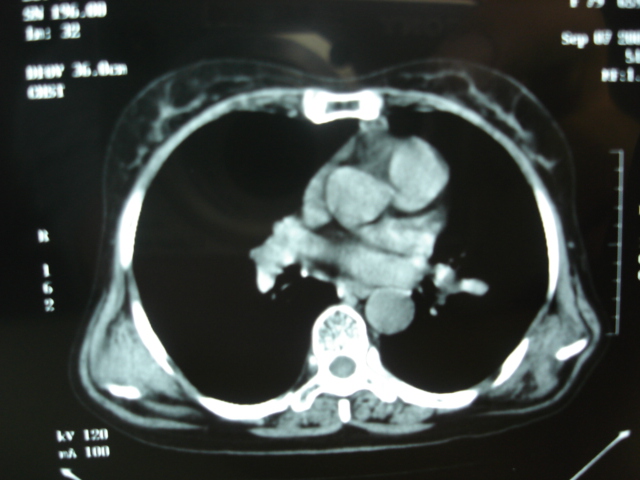

以下是引用卜一在2009-9-7 19:51:00的发言:[br][br] 1 左侧胸内甲状腺占位-多考虑甲状腺腺瘤! 2、左肺门占位-建议增强扫描以便明确性质。 3 慢支并感染! [br]

以下是引用shibing在2009-9-7 20:40:00的发言:[br]左侧胸内甲状腺占位-多考虑甲状腺腺瘤! 2、左肺门占位-建议增强扫描以便明确性质。 3 慢支并感染! [br]